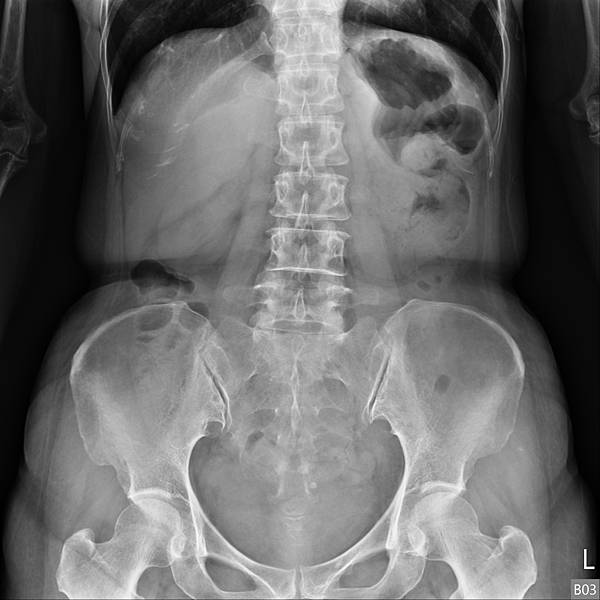

她的問題出在腸道產氣細菌製造出來的腸氣影響(抑制)大腸蠕動,大腸蠕動慢,吸收水分多,造成升結腸的糞便因水分吸收過多而呈羊屎狀。解決方式是「清腸+益生菌」,兩週後的X光片如下: